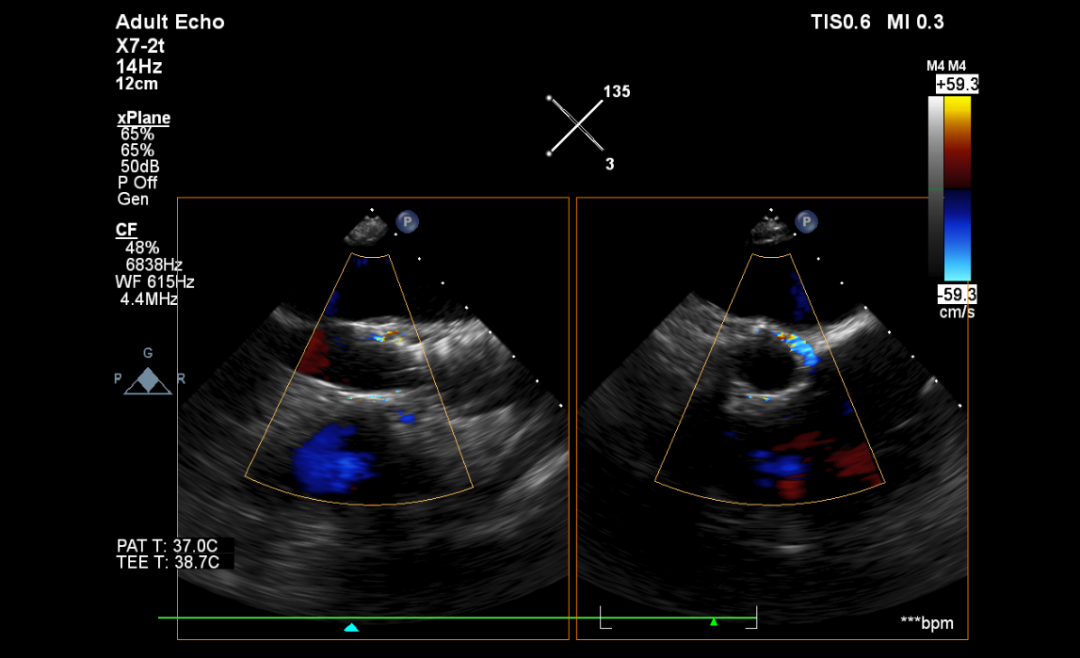

术前预案

手术过程

右冠保护

反复造影确认冠脉风险